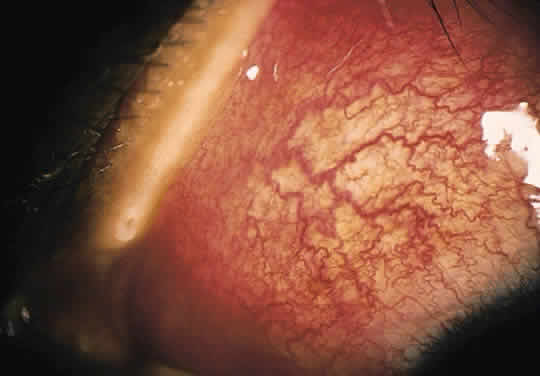

Sarcoidosis remains a systemic granulomatous condition of unknown etiology. It is recognized by histologic appearance and clinical features and sometimes by exclusion of other etiologies. The granuloma formation is probably a final common tissue response pathway to many different antigens that are not readily cleared from the tissue. The histologic pictures of diseases associated with a number of environmental agents, such as beryllium, pine dust, or peanut dust are similar to those of sarcoidosis.58,59 This seems to be a reasonable explanation for the inability to find one specific causative agent despite the relative frequency of the disease, which is estimated to be between 30 and 64 per 100,000 based on clinical examination. Autopsy studies, however, show that the true incidence may be 10 times this rate, suggesting that most cases go undiagnosed.60,61 Fatigue is sometimes the only symptom of systemic involvement. Skin lesions, conjunctival granulomas (Fig. 7), lymph node biopsy specimens, and other involved tissues show high CD4+ T-cell concentrations in epitheloid cell noncaseating granulomas. Certain body compartments may be more involved, and systemic circulating T-cell populations or other systemic indicators of inflammatory activity may show no abnormality. The diagnosis may be easier when the chest x-ray shows the typical mediastinal lymph node enlargement, or when systemic levels of angiotensin-converting enzyme or serum lysozyme are elevated.62–64 Genetic factors apparently play a role, and immune complexes have been noted; however, these influences remain to be clarified.

Fig. 7. Conjunctival nodules in patient with sarcoidosis.